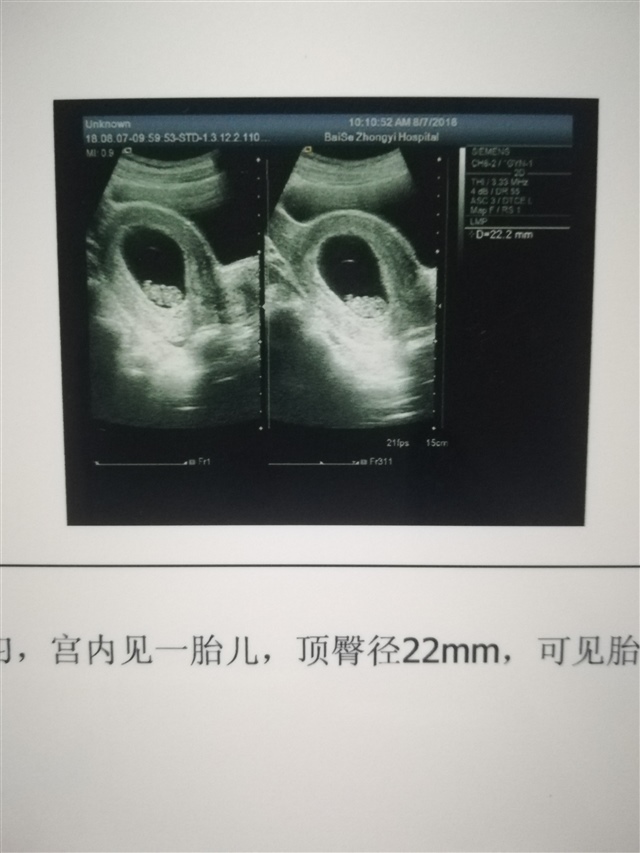

孕9周+4天